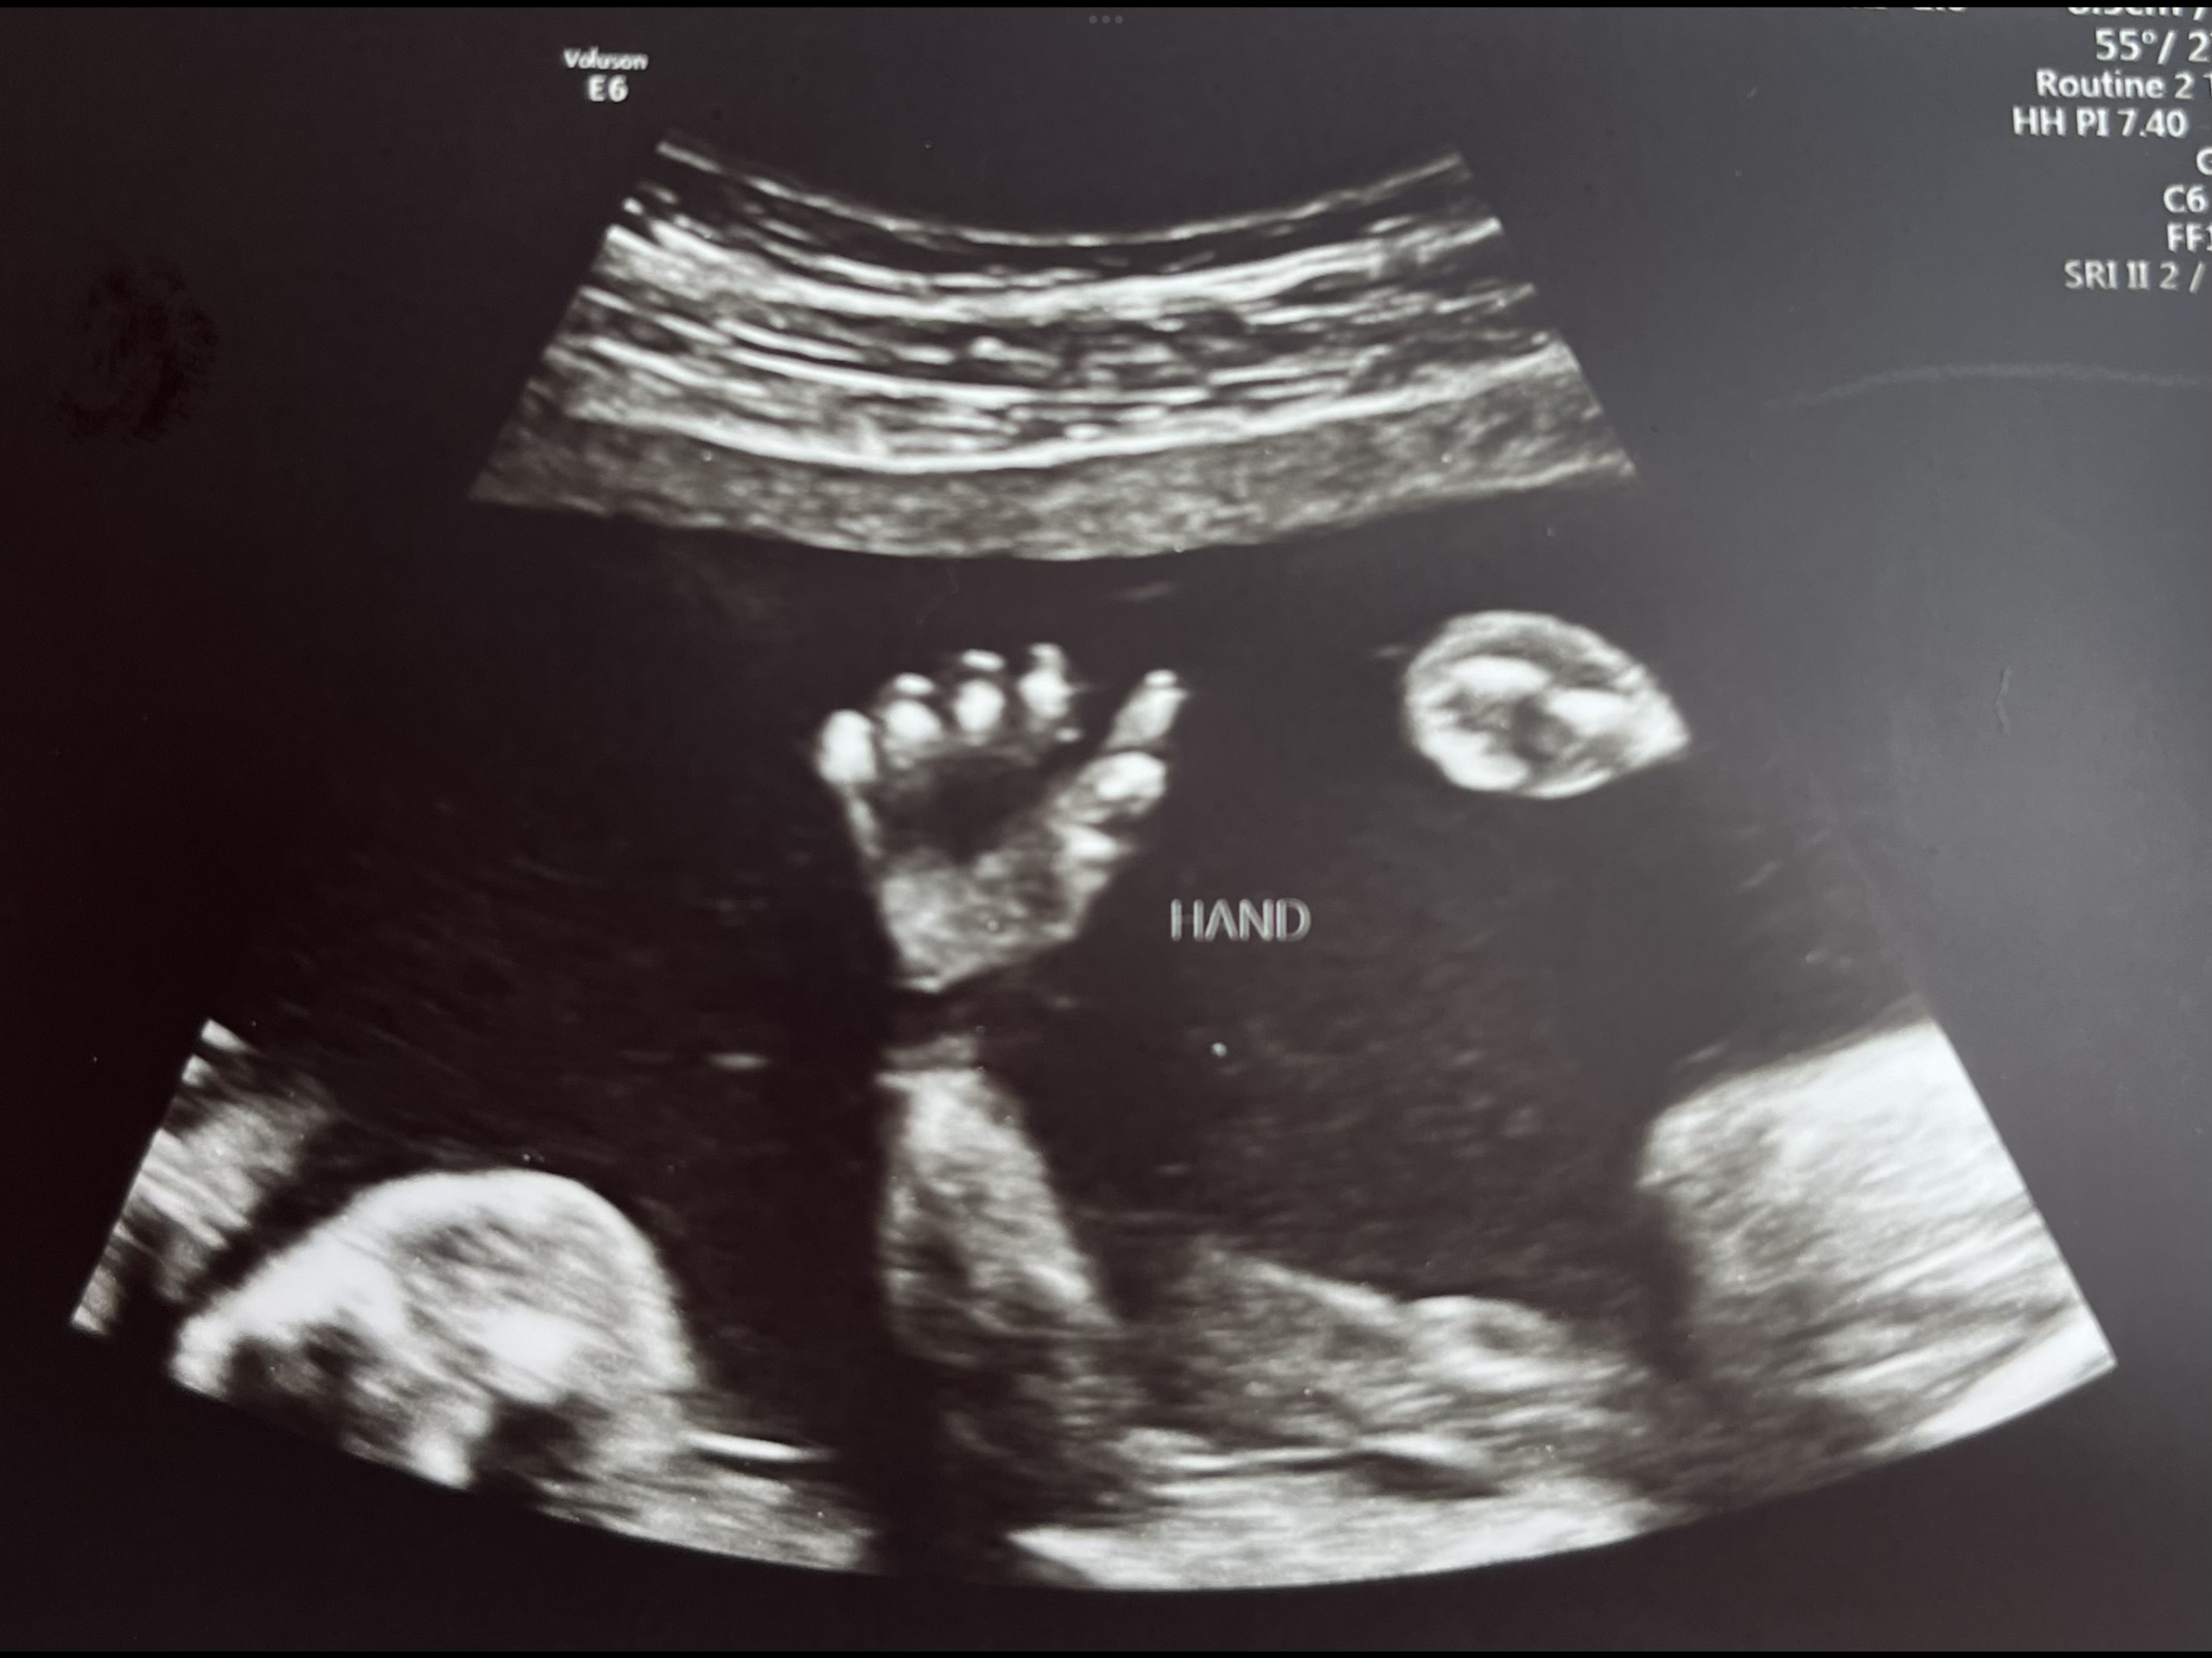

I’m stealing Charlie Kirk’s response from his many debates on abortion. (Here is a great video of him explaining his thoughts). Put 2 ultrasound pictures next to each other, one from a mother who was raped and one from a mother in a loving relationship. There’s no difference, right? So why does one baby deserve to live and the other doesn’t? If the mother does not want the baby or feels she won’t be able to adequately care for the baby, adoption can be an amazing solution! According to American Adoptions, there are approximately 2 million families waiting to adopt. I’m not saying the pregnancy/giving up the baby won’t be hard, I’m sure it will be. But the baby will be given the opportunity for life, and a family will be blessed by them.